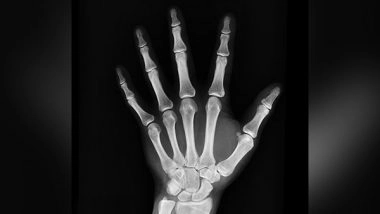

Osaka [Japan], February 27 (ANI): Bone remodeling occurs in different parts of the body throughout life to maintain bone physique balance and systematic mineral homeostasis. During this "remodeling" process, osteoclasts remove mineralized bones, whereas osteoblasts form new bones. These resorption and formation phases are linked and balanced with intermittent coupling phases.

Osteoblasts are the cells that are required for bone synthesis and mineralization during the initial formation of bone and during bone remodeling. They act in a group to make bone over the course of several months. But, how osteoblasts cooperate with each other in vivo is still unknown.

According to new research led by Osaka University established an advanced high-resolution microscopy system to see extracellular vesicles secreted and captured by mature osteoblasts in vivo and identified a subset of osteoblast-derived vesicles which can limit bone formation and stimulate bone-resorbing osteoblast differentiation through a mircroRNA (miRNA)-mediated mechanism. The osteoblast communication via extracellular vesicles controls the dynamic transition from bone-forming to bone-resorbing phases in vivo and could be a target for new treatments for bone diseases.

"Functional coupling between these two cell types is critical for the maintenance of proper bone metabolism, and the mechanisms controlling the transition from bone-resorbing to bone-forming phases have been investigated. Nevertheless, the molecular and cellular mechanisms terminating osteoblastic bone formation and promoting osteoclastic bone resorption remain elusive," explained senior author Masaru Ishii.

Intravital optical imaging using multiphoton microscopy can help dissect in vivo cellular dynamics in various intact tissues and organs. To understand the spatiotemporal dynamics of bone remodeling in vivo, the researchers have established an intravital imaging technique to visualize the intact bone tissues of living mice. Using this method, they explored the interplay between bone-destroying osteoclasts and bone-forming osteoblasts. However, the spatial resolution of intravital bone imaging was insufficient to visualize structures smaller than cells.

"In this study, we established an advanced high-resolution microscopy system to visualize extracellular vesicles secreted and captured by mature osteoblasts in vivo and identified a subset of osteoblast-derived vesicles limiting bone formation and stimulating osteoclast differentiation, thus regulating the switch from bone formation to bone resorption through a microRNA (miRNA)-mediated mechanism," said Ishii. (ANI)